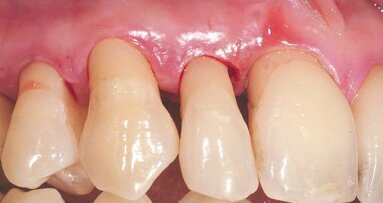

A 38-year-old female patient consulted owing to moderate pain associated with her previously treated maxillary right second premolar. Her medical history was non-contributory. Clinical examination revealed that the tooth was slightly sensitive to vertical percussion. Periodontal probing depth and mobility were within normal limits. A periapical radiograph showed the presence of a separated instrument outside of the root (Fig. 2a), and a preoperative CBCT scan demonstrated that the buccal bone plate was intact (Figs. 2b & c). Endodontic retreatment had been performed five months earlier. The diagnosis for tooth #15 was previously treated symptomatic periapical periodontitis, and the treatment of choice was guided EMS.